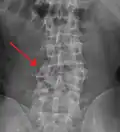

A burst fracture of L4 as seen on plane X ray -

A burst fracture of L4 as seen one plane X ray -